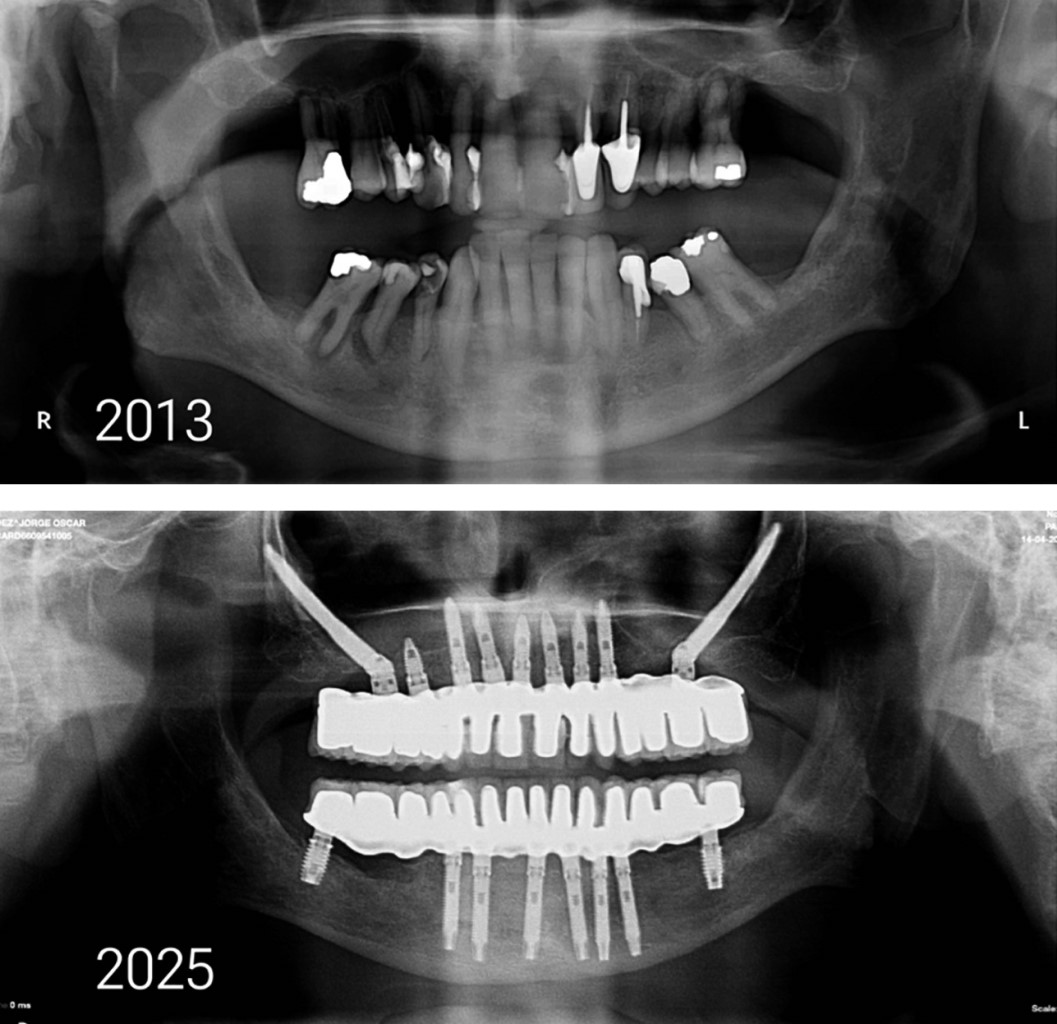

Tal es el caso de la paciente femenina de 50 años, edéntula total desde los 27 años, quien consultó por alteración severa de la estética facial, dificultades masticatorias y sensación de envejecimiento prematuro. El examen clínico evidenció colapso del tercio inferior facial, pérdida de la dimensión vertical y signos avanzados de SEOP (Figura 4). La visión de perfil mostraba retrusión maxilar; incluso con prótesis, el rostro mostraba hundimiento de mejillas y surcos nasogenianos. Sin prótesis, se acentuaban la flacidez y la expresión facial senil. La tomografía volumétrica mostró atrofia maxilar severa con neumatización sinusal, y antecedentes de sinusitis crónica contraindicaron la colocación de implantes cigomáticos intrasinusales.

Se decidió un abordaje combinado con osteotomía tipo Le Fort I, con avance maxilar de 10 mm, y colocación de implantes yuxtaóseos personalizados, planificados digitalmente con base en la anatomía remanente. Esta decisión quirúrgica se justificó por la precariedad volumétrica de los huesos malares, que impedía el anclaje bicortical cigomático, sumado a la contraindicación por patología sinusal crónica (Figuras 4, 5, 6 y 7). El procedimiento fue realizado bajo anestesia general, sin complicaciones, utilizando guías quirúrgicas. La cirugía concluyó con procedimiento complementario de ritidectomía (Figura 8).

Se realizó carga diferida con prótesis fija atornillada con base en titanio y revestida con circonio. En el control a los seis meses, se observó recuperación del soporte labial, armonía de los tercios faciales y desaparición de los pliegues periorales (Figuras 9 y 10).